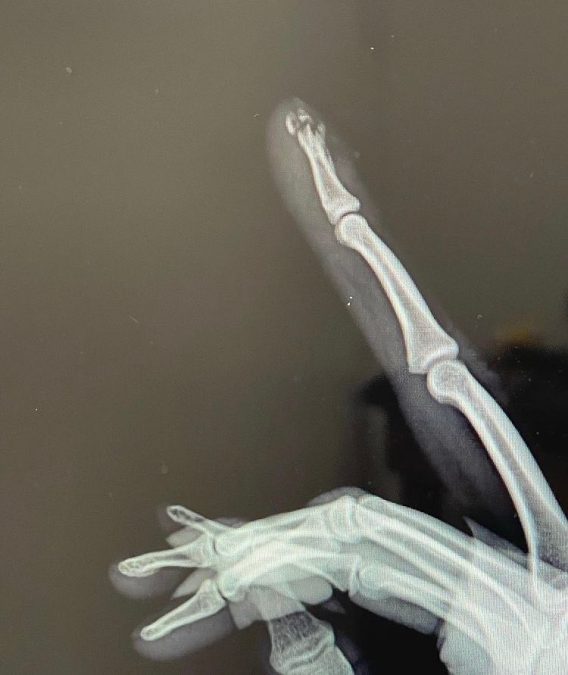

El mexicano Ángel Martínez compartió a través de sus redes sociales la noticia de que entrenando en el gimnasio se le cayó una pesa sobre su mano y tuvo una fractura expuesta en uno de sus dedos. Algo parecido a lo que le sucedió al británico Adam Peaty mientras entrenaba en Tenerife, aunque en ese caso fue una fractura en un dedo del pie.